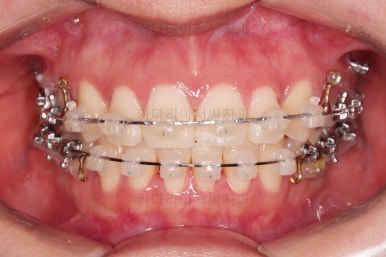

틈이 다 없어졌고, 교합도 양호합니다.

무엇보다 임플란트 없이 결손부위가 깔끔하게 채워졌고요.

전후 비교 해볼게요.

입안의 모습은 더할나위 없이 잘 개선되었고요.

상하좌우 이 뽑은 위치와 크기가 달라 이정도 중앙선은 매우 잘 맞는 상황인거고요.

얼굴모습도 옆라인이 매우 좋아졌죠.

입이 들어가고 턱선이 살아나게끔 해드렸어요.

임플란트도 안해도 되면서 사랑니까지 잘 사용하고 2년 반 밖에 치료기간도 안걸린 매우 좋은 치료였다고 생각되어집니다.

이상 어금니가 결손되어 있고, 돌출입이었던 환자분을 미니스크류를 이용해 사랑니까지 당겨와서 임플란트 없이 치료를 한 부산사랑니교정 치료사례였습니다.